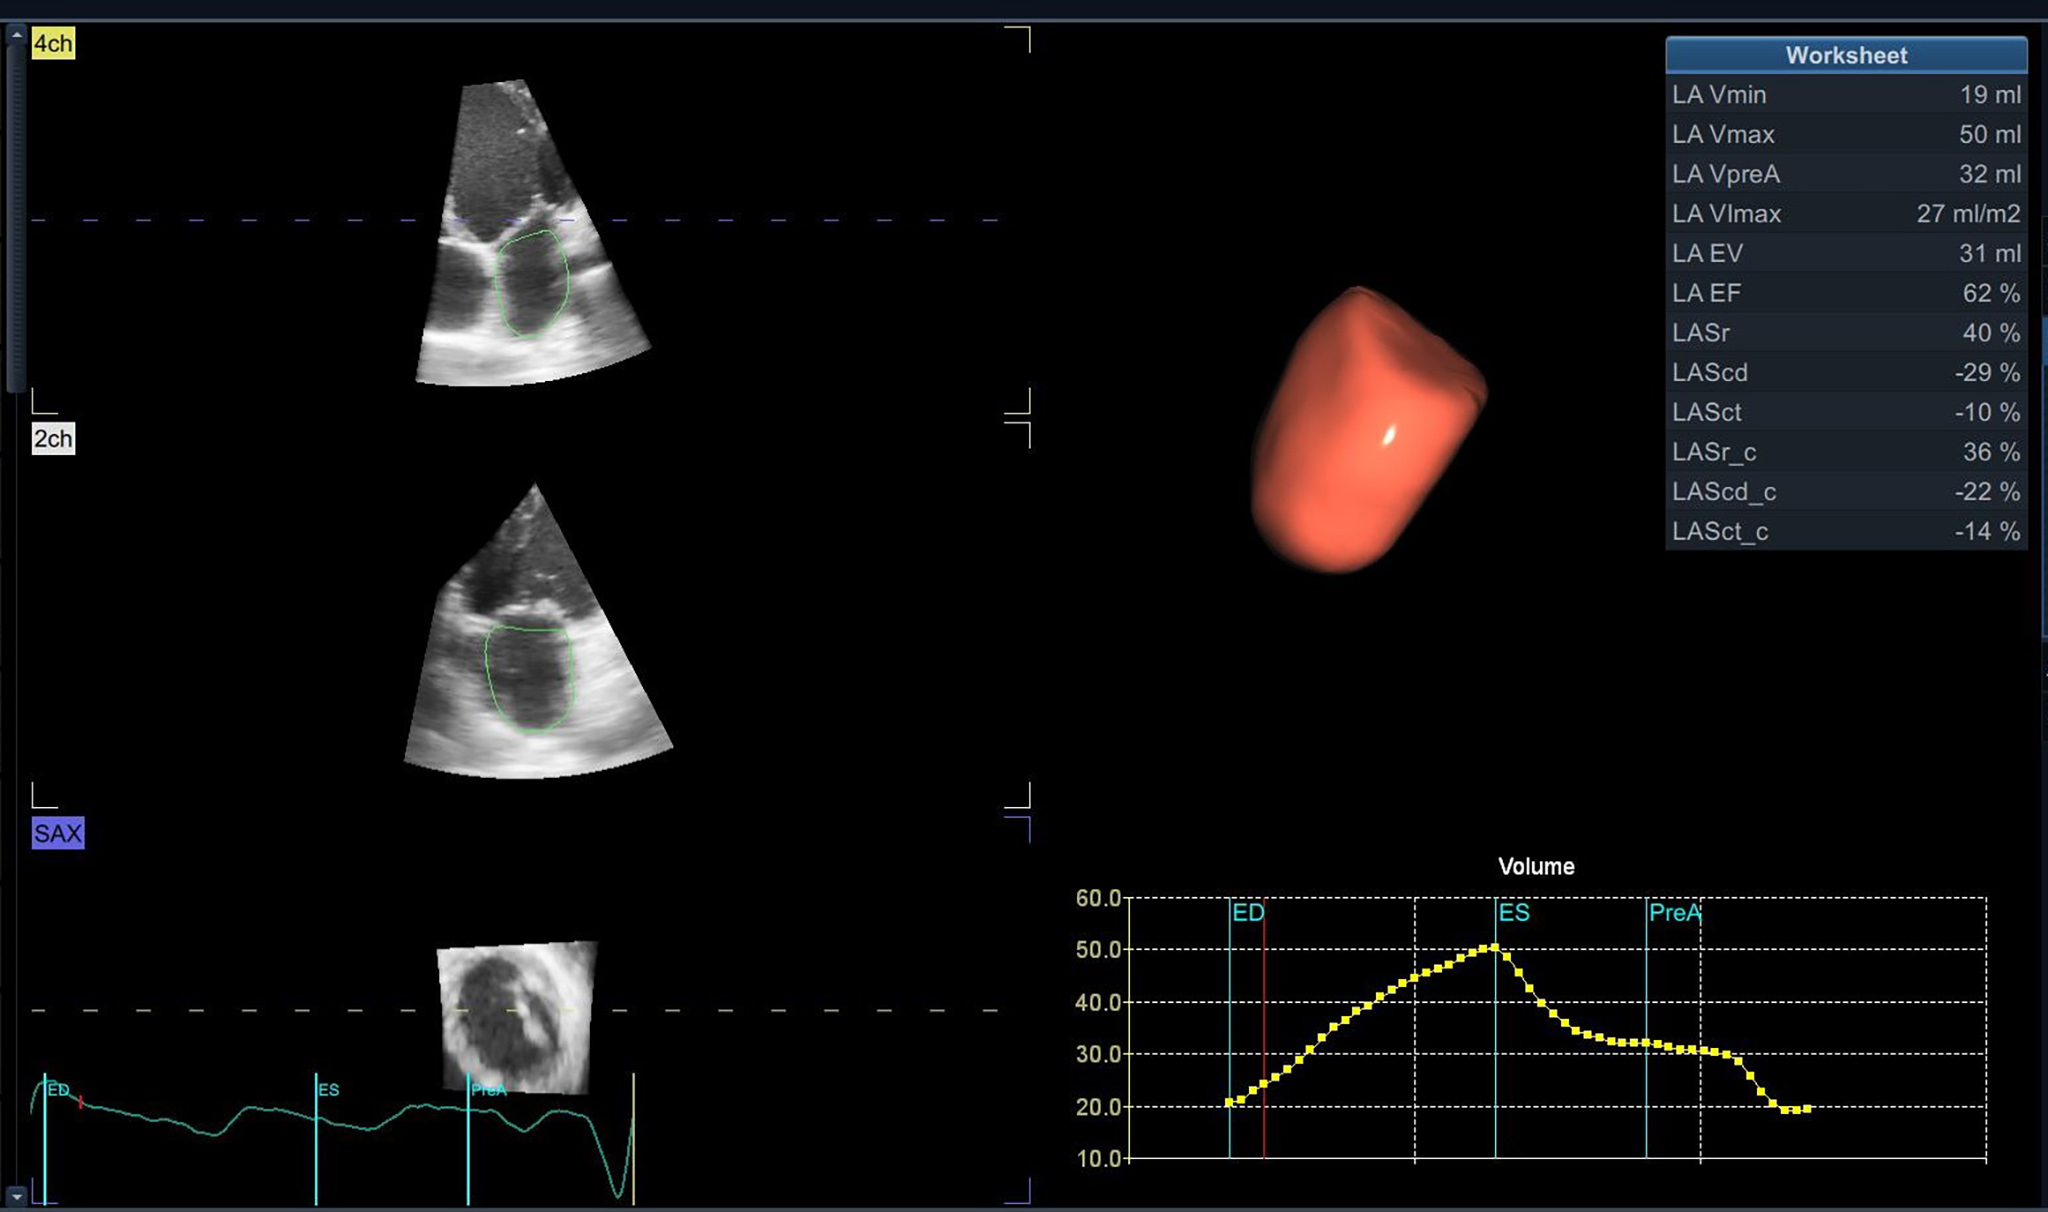

Fig. 3.

Fig. 3.Left atrium tridimensional volume and function using 3D-E speckle tracking with a dedicated software.

The maximum volume is the most evaluated parameter associated with AF [30, 31, 39], but more recent studies concentrated on LA minimum volume as a marker of prognosis [40, 41, 42, 43]. Appleton et al. [44] showed that minimum LA volume is more closely related to left ventricular filling pressures evaluated invasively, compared to maximum LA volume. In patients with paroxysmal AF, LA remodeling evaluated by both 2D-E and 3D-E is strongly associated with AF episodes, that are best predicted by LA minimum volume [40]. Minimum LA volume seems to be an independent predictor of a first tachyarrhythmia episode [41, 45]. Nevertheless, the LA maximum volume is more reproducible in terms of inter-observability when measured in 2D-E [41], and even 3D-E [38].

When therapeutic strategies are applied in the early stages of the development of paroxysmal episodes [46, 47], by lowering the AF burden and maintaining the sinus rhythm (SR), the LA will present a reverse remodeling process [25, 28, 48]. Atrial fibrillation ablation, especially in patients with “lone AF”, in the absence of structural cardiac disease, will determine reverse atrial remodeling [49]. Reports define LA reverse remodeling as a decrease of more than 15% in LA index volume, compared to baseline values, assed by TTE [28]. The process of reverse remodeling is reported with 2D-E studies [25, 28, 46, 48], but also with 3D-E studies. Even if 3D-E is not largely available in clinical practice, it seems to be a feasible and reproducible imaging method also for in-training echocardiographers [50], while providing more accurate values of the true LA dimensions, as compared with cardiac magnetic resonance evaluations [51, 52]. A limitation for 3D-E refers to patient cooperation, high imaging quality, and frame-stitching over consecutive regular cardiac cycles, making evaluation for AF patients during arrhythmias inconclusive [45].

In conclusion, the most useful anatomical parameter to characterize AF propensity should be LA volume and mainly LA indexed volume. Assessment of LA volume is best performed by 3D-E, should both ultrasound hardware and software be available and echocardiographic views accurate.